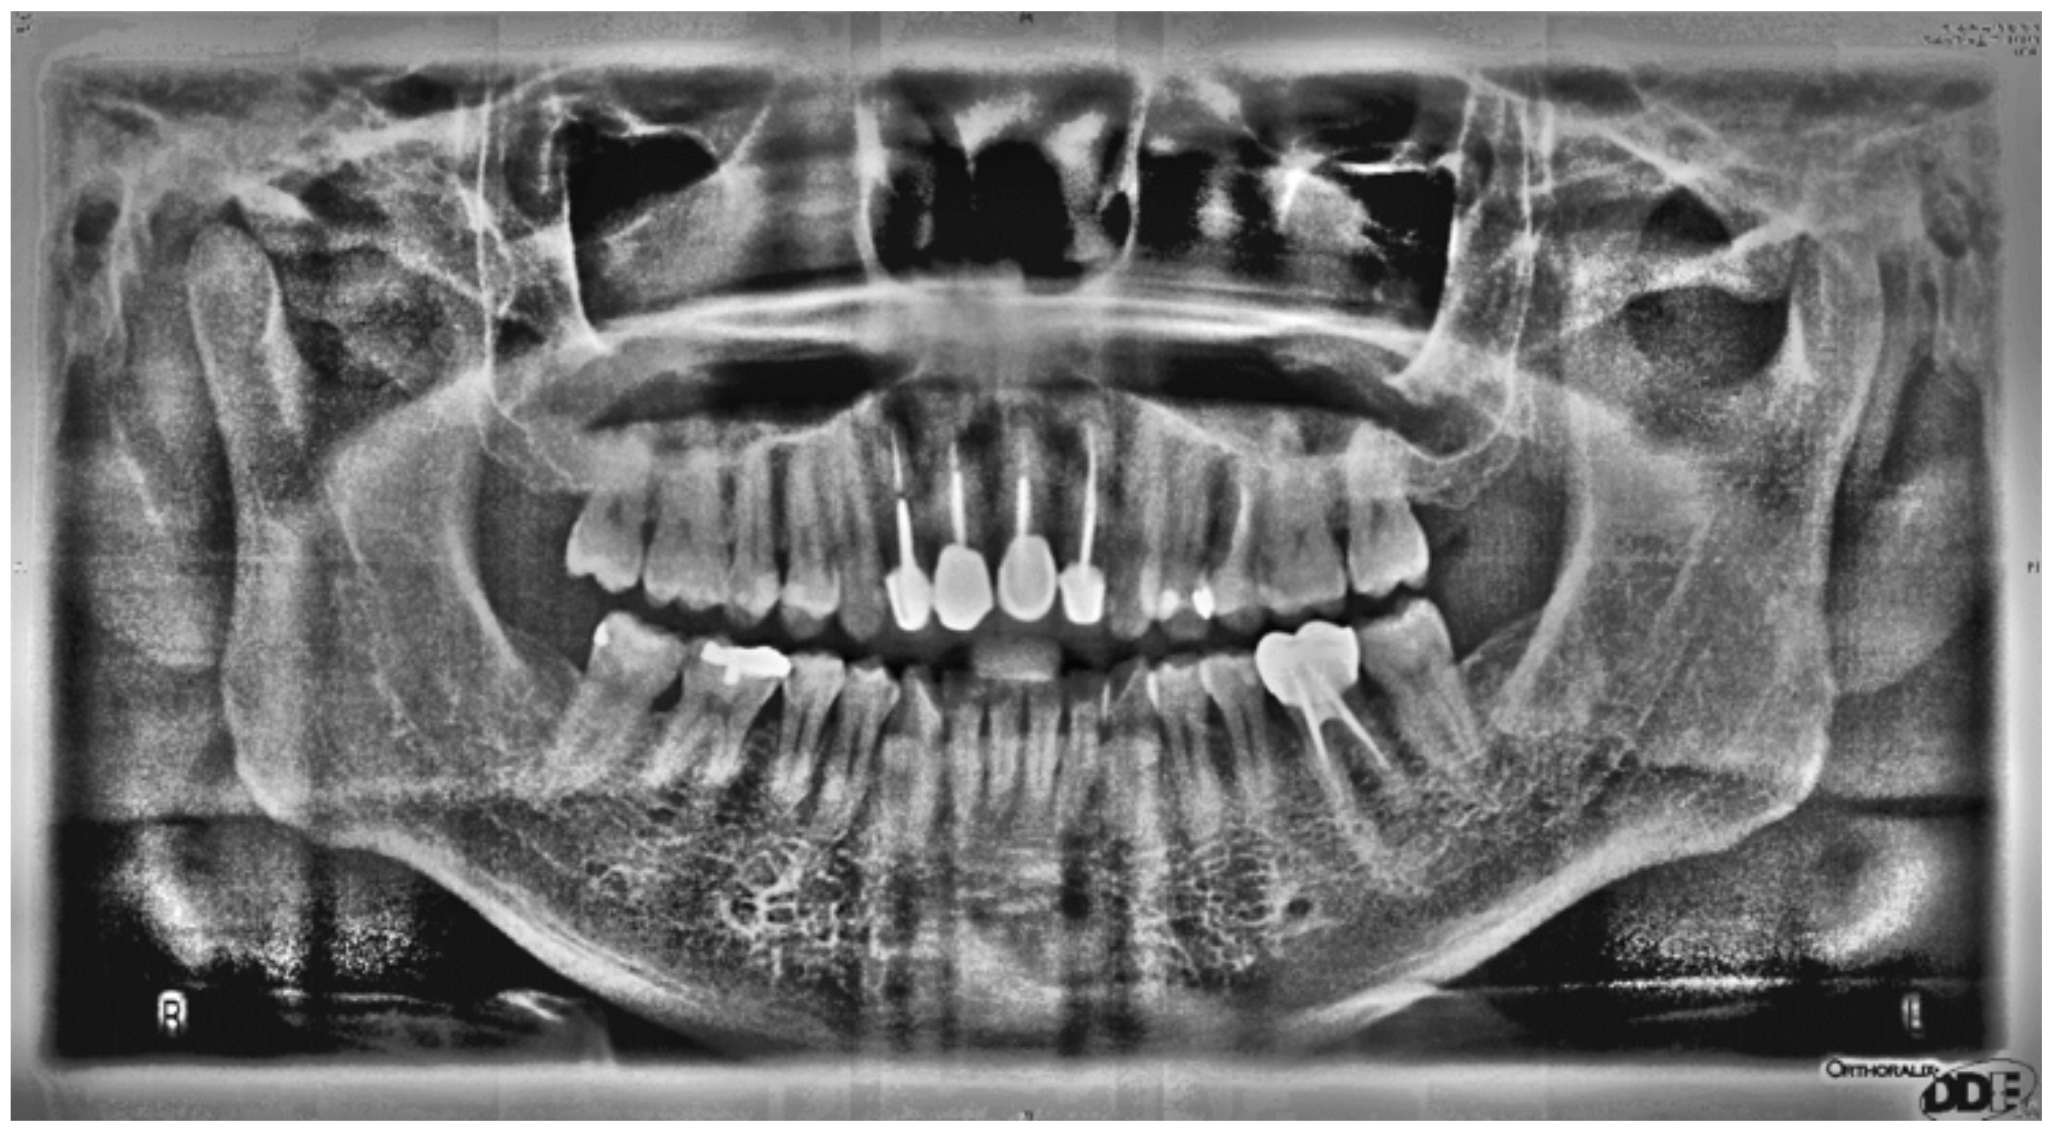

2.1.1. Sharpening

2.1.2. Image Contrast Adjustment

2.1.3. Flat-Field Correction

2.1.4. Adaptive Histogram Equalization

| Image Enhancement in Cutting Accuracy Rate | |||||

| Original Image | Matrix Operation Diagram | Image Contrast Adjustment | Flat-Field Correction | Adaptive Histogram Equalization | |

| Cutting accuracy rate | 34.72% | 51.68% | 58.74% | 78.61% | 89.95% |